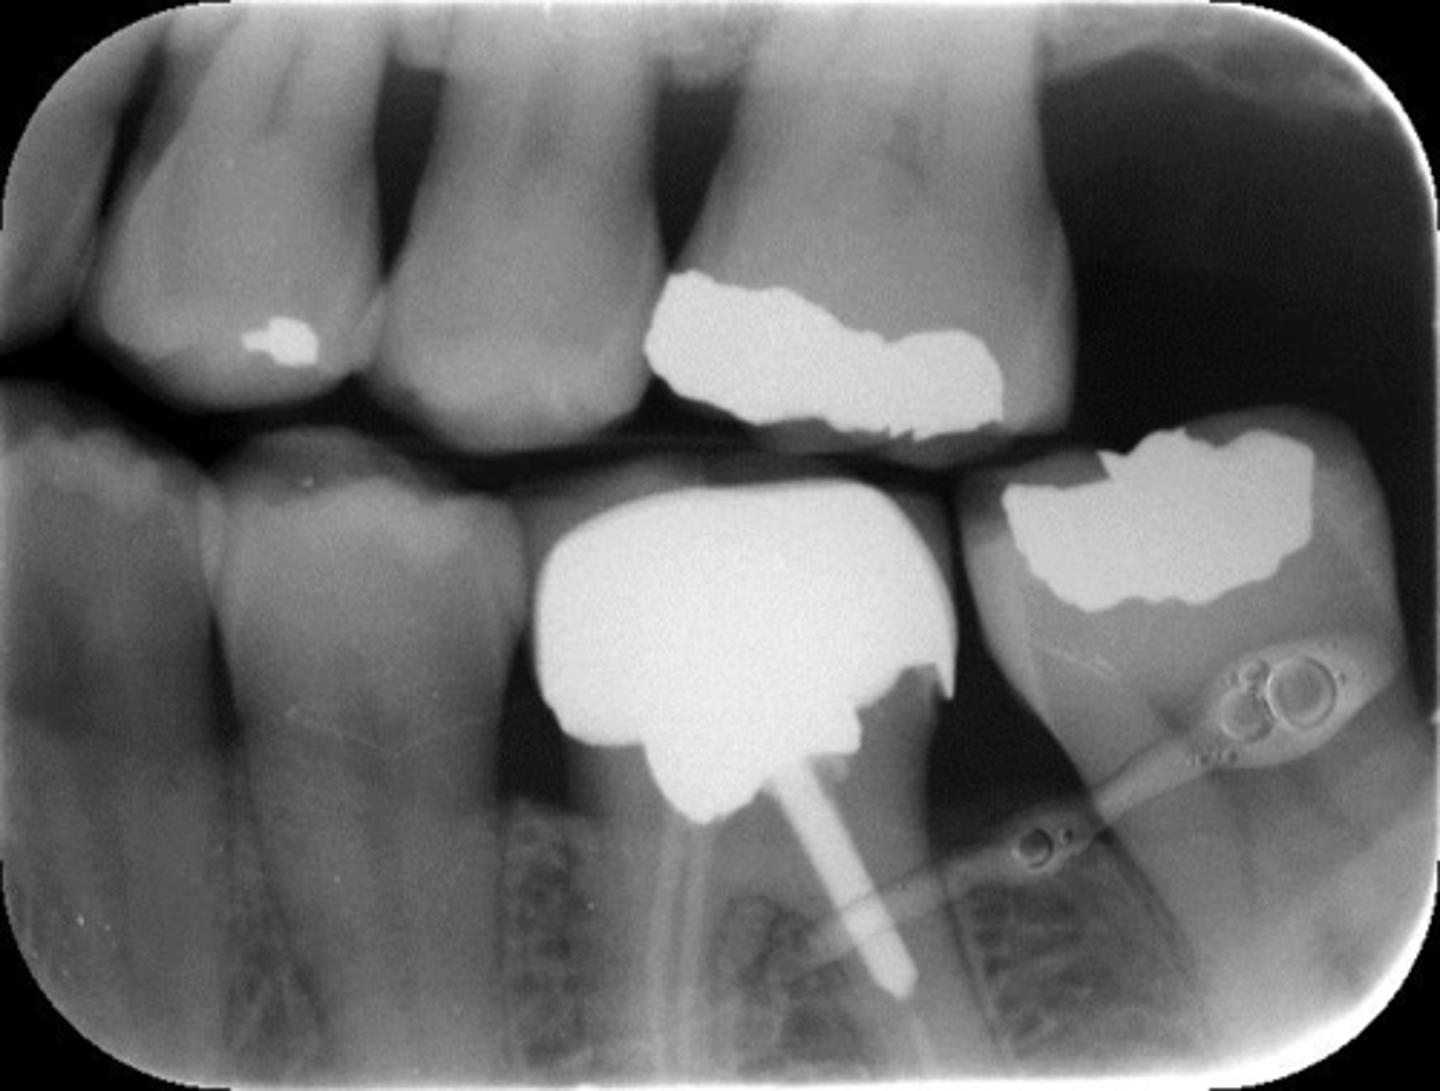

What is this error?

Moisture contamination

Elongated, vertical angulation, film holder (metal bar)